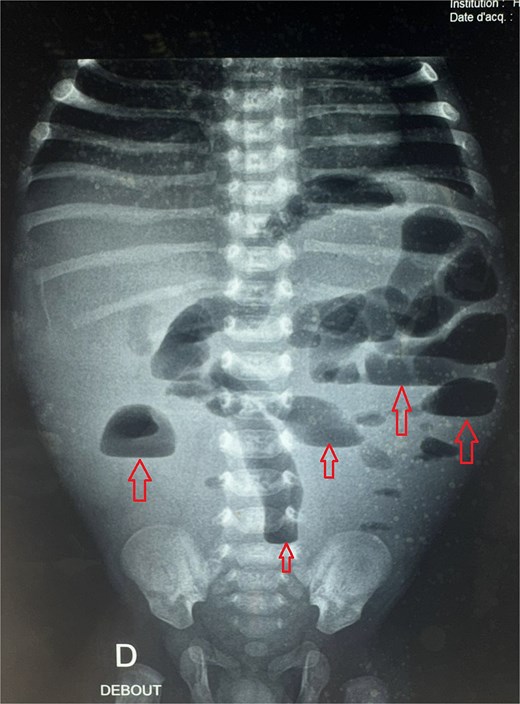

A male neonate was admitted at 47 h of life with signs of severe respiratory distress requiring immediate intubation. Physical examination revealed a distended abdomen, a prominent thoracic contour, and diminished breath sounds on the left side. A thoraco-abdominal X-ray showed multiple air-filled intestinal loops in the left hemithorax, consistent with a CDH. The patient underwent a primary repair of surgical repair of his diaphragmatic defect (Fig. 1). The initial postoperative course was complicated by multiple episodes of bowel obstruction. Postoperative radiographs demonstrated multiple air-fluid levels without evidence of significant colonic dilatation (Fig. 2). The patient underwent reoperations on postoperative days 21 and 50. Intraoperative findings revealed early adhesions without evidence of other anomalies. Adhesiolysis was performed on both occasions. The patient was discharged on postoperative day 60. At 3 months of age, the child was readmitted with signs of recurrent intestinal obstruction, including bilious vomiting, absence of stool and gas passage, and abdominal distension. The mother reported that spontaneous bowel movements occurred only after the administration of suppositories. Additionally, the child exhibited failure to thrive, with a weight below −2 standard deviations for age. The child had no facial dysmorphism or abnormalities of the limbs or nails.

Postoperative abdominal radiograph demonstrating multiple air-fluid levels (arrows) without evidence of significant colonic dilatation.